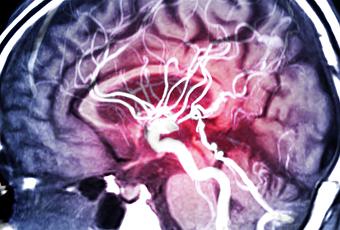

Un diabète de type 2 préexistant est lié à de moins bonnes performances cognitives après un accident vasculaire cérébral (AVC), soulignent ces chercheurs de l’Université de Nouvelle-Galles du Sud (Australie). Ces travaux, présentés dans Stroke, une revue de l’American Heart Association, confirment des preuves déjà solides d’une association entre le diabète de type 2 et une déficience cognitive, alertent à vérifier la capacité du patient, post-AVC, à contrôler son diabète et incitent à détecter les premiers signes de prédiabète afin d‘éviter ou de retarder ces complications cérébrales et cognitives.

Ainsi, les personnes atteintes de diabète de type 2 présentent de moins bonnes performances cognitives 3 à 6 mois après un AVC, par rapport à des patients non diabétiques. Au-delà relation entre diabète et cognition est complexe : le diabète de type 2 augmente le risque d’AVC et a déjà été associé à des troubles cognitifs ainsi qu’à un risque plus élevé de démence.